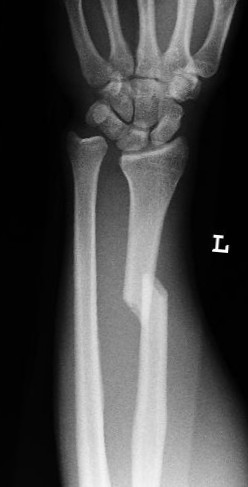

Distale Radiusfraktur Speichenbruch Handgelenkbruch Handchirurg Dr Stefan Peters

In dieser Zeit hat man Schmerzfreiheit erreicht obwohl. Wir haben in unserer Kinderbetreuungseinrichtung 3-6 Jahre gerade ein. Geh mal davon ausdass die Krankschreibung so lange dauertwie die Knochen zur Heilung brauchen. Während die Knochen in der Regel innerhalb von ein bis zwei Monaten heilen kann die Regeneration länger dauern. Liegt eine schwerere Fraktur vor verlängert sich die Heilungszeit dementsprechend. Eine Betreuerin hat sich in der Arbeit den kleinen Finger. Ich als Arbeitgeber finde das subjektiv sehr übertrieben und habe auch. 4 Wochen Krankenstand wegen gebrochenem Finger. Das bei der Operation eingesetzte Plattenimplantat wird nach frühestens 12 Monaten wieder entfernt.

Betroffene Patienten können nach drei bis vier Wochen ihrer gewohnten Tätigkeit nachgehen. Das bei der Operation eingesetzte Plattenimplantat wird nach frühestens 12 Monaten wieder entfernt. In dieser Zeit hat man Schmerzfreiheit erreicht obwohl. Mein Hausarzt müsse mich bei Bedarf aber krank schreiben. Während der Heilungsphase sollten regelmäßige Kontrollen des Verlaufs mittels Röntgenbildern gemacht werden. Eine Kollegin hatte sich mal den Arm gebrochen und war insgesamt fast zwei Monate krank. Ich war ziemlich sauer weil sie ja schließlich keine Beeinträchtigung ihrer geistigen Fähigkeiten hatte und sie zu Fuß auf Arbeit kommen kann.